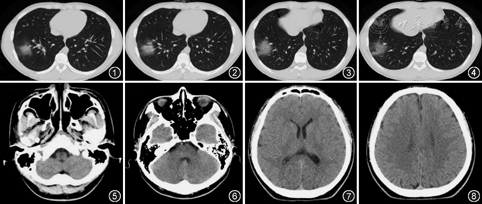

病例1 患者男,18岁,于2020年3月26日从加拿大回国,回国后隔离期间出现发热伴咳嗽、咳痰、咽干,体温最高38.6 ℃,2020年4月3日咽拭子新冠病毒核酸检测阳性,收入我院。患者6年前有EB病毒肺炎病史,入院后体检:体温36.9 ℃,脉率107次/min,呼吸频率21次/min,血压134/94 mmHg(1 mmHg=0.133 kPa),SpO2为95%(未吸氧状态),神志清楚,咽部充血,双肺呼吸音粗,未闻及明显干湿性啰音,心、腹未见异常。外院查血白细胞为5.96×109/L,中性粒细胞百分比为60.6%,淋巴细胞绝对值为1.2×109/L,C反应蛋白为0.89 mg/L。胸部CT示右肺下叶片状磨玻璃样高密度影,初步诊断:新型冠状病毒肺炎。给予阿比多尔片0.2 g,3次/d,口服抗病毒、乙酰半胱氨酸片600 mg,2次/d口服对症治疗。入院后胸部CT如图1~4。

患者入院第6天,自诉嗅觉丧失,伴轻咳,给复方甘草合剂10 ml,3次/d,口服对症治疗,暂观察嗅觉情况。第8天患者仍旧诉嗅觉丧失,请耳鼻喉科会诊,给予甲钴胺0.5 mg,3次/d,口服营养神经,每天自行75%的酒精测试恢复情况,入院第15天患者仍诉嗅觉减退,对症治疗效果欠佳,专家组会诊后考虑不除外病毒侵犯嗅神经,加用维生素B1 10 mg,3次/d,口服对症,行鼻窦CT(图5,6)、头颅CT(图7,8)检查均未见明显异常,再次请耳鼻喉科专家会诊,考虑不除外神经性损害或嗅上皮损害,建议加用牛痘疫苗接种家兔炎症皮肤提取物8 U,2次/d肌肉注射。患者嗅觉有一过性好转,但恢复缓慢,于入院第20、21天行咽拭子新冠病毒核酸检测均为阴性,出院继续观察。出院后5个月电话随访,患者嗅觉于出院后未恢复至发病前状态,仍有轻度嗅觉减退,因未影响日常工作及生活未进行诊治。